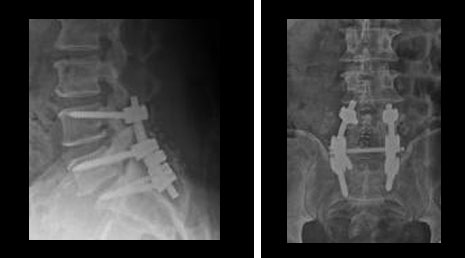

38. Lumbar dynamic stablization